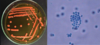

Con este cultivo y examen directo se llega al diagnostico de:

Aspergilus flavus

Diagnostico que se llega mediante este cultivo y examen directo:

Aspergilus flavus

Colonia verde aterciopelada

Conidioforos largos

Fialides en 360° con dos series de fialides